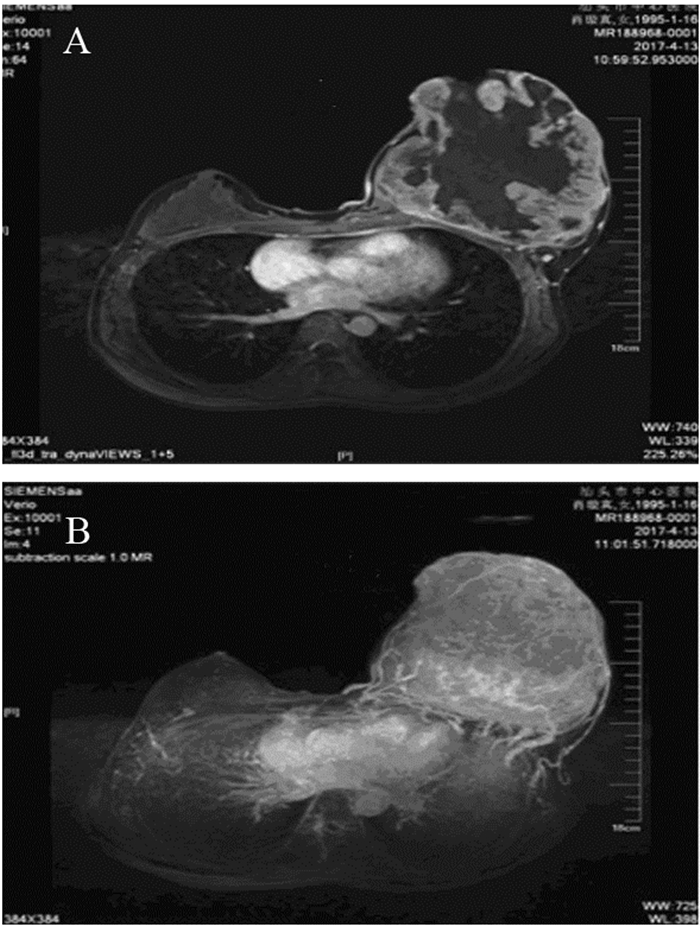

第一,无痛单发的小肿块,很多人常常在无意间触摸到小肿块,遗憾的是,很多人并没有引起重视,她们误把乳腺癌当成了小叶增生,结果可想而知,随着时间的推移,肿瘤很可能会发生转移。

第二,局部隆起,随着肿块越来越大,可以引起局部隆起,这个时候,往往能够发现左右不对称,如果这个时候,你依然不重视,肿瘤将很快发生远处转移。

事实上,大部分乳腺癌的患者,可能都是第一种表现,如果这个时候,你没有及时触摸到异常的肿块,或者触摸到也没有引起重视,就可能导致乳腺癌不断进展。

后面三种表现相对比较突出,遗憾的是,有些乳腺癌,并不会出现这些症状。